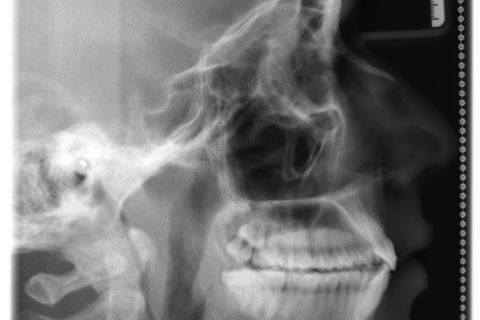

Final RX Cef.

Paciente: Sexo masculino, 16 anos

Diagnóstico: Classe II, divisão 2

Sugestão de Tratamento: Tratamento ortodôntico com o uso do sistema de alinhadores removíveis Invisalign. Sem extrações dentarias, pois o perfil do paciente não era favorável. Por ser um paciente jovem, optou-se por uma expansão dentária controlada, buscando a remodelamento dos arcos.